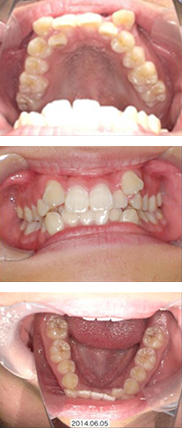

全体矯正症例

16才 女性

顎の成長が終了してから抜歯を行い、スペースを確保してそこにゆっくりと歯を移動させていきます。

歯並びも咬み合わせも整い、無事に矯正装置を外すことができました。

矯正前

矯正中

矯正後